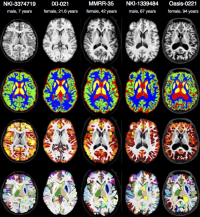

ANT-2

Within this project, clinically acquired magnetic resonance imaging (MRI) brain data of the past years is processed retrospectively. Using these data the primary task is to create a brain template with the Advanced Normalization Tools (ANTs) which will serve as a reference in diagnosis in neurodegenerative and psychiatric diseases. Beyond this, further tasks may vary depending on the individual skillset and type of work.